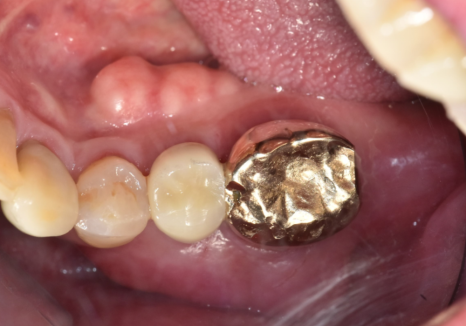

두 번째 사례, 8개월 뒤 다른 금니가 또 빠진 환자분

상일역 치과, 오래된 금니 빠짐

임플란트 치료가 잘 끝나고 8개월 뒤...

환자분께서 또다시 저희 병원을

내원하셨습니다.

250822

이번엔 반대쪽인

왼쪽 아래 어금니인 금니가

'툭' 하고 빠지신 건데요.

지난번 발치의 아픈 기억 때문인지,

"이번에도 뽑아야 하나요...?"

하며 걱정이 태산 같으신 모습이었습니다.

조심스럽게 빠진 자리를 살펴보니,

역시나 치아 내부에

까맣게 충치가 진행되어 있었죠.

하지만..

엑스레이와 구강 상태를 꼼꼼히 확인해 보니,

이번 치아는 다행히

발치 없이 충분히 살려서 쓸 수 있는 상태였습니다.

이번 케이스가 지난번과 달랐던 결정적인 차이,

바로 금니 표면의 '구멍' 유무였습니다.

250905 상일역치과, 오래된 금니 빠짐

하지만 천만다행인 점은,

첫 번째 사례처럼 구멍을 통해

음식물 찌꺼기가 직접적으로

유입되는 최악의 상황은 아니었다는 사실!

덕분에 치아 내부가

힘없이 바스러질 정도로

심각하게 손상되지는 않았고,

뿌리 쪽 뼈 상태도 염증 없이

깨끗하게 유지될 수 있었습니다.

240812

충치가 있긴 했지만

치아 뿌리는 튼튼했기에,

치아 내부의 오염된 신경관을

청소하는 신경치료를 진행했습니다.

251010

오염된 신경을 4번에 걸쳐

꼼꼼히 제거하고 소독한 뒤,

이번에는 구멍이 잘 나지 않는

단단한 재료인 '지르코니아'로 씌워,

튼튼하게 마무리해 드렸습니다.

251103